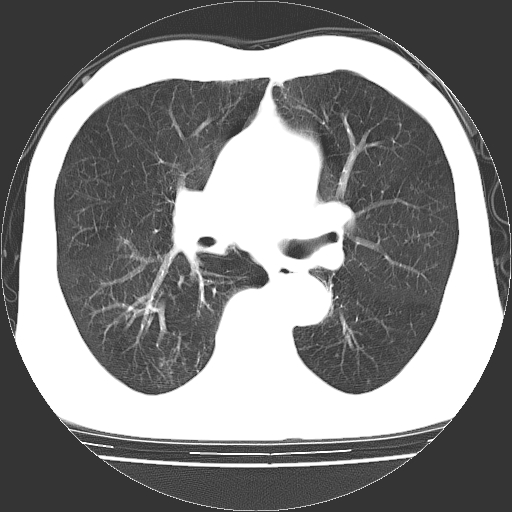

以下是引用hhcckk在2009-1-1 15:38:00的发言:[br]左下肺少许絮状模糊影--考虑感染[br]两肺散在小点状密度增高影--结合病史考虑矽肺?[br]气管壁钙化--可能由于老年退变性引起的